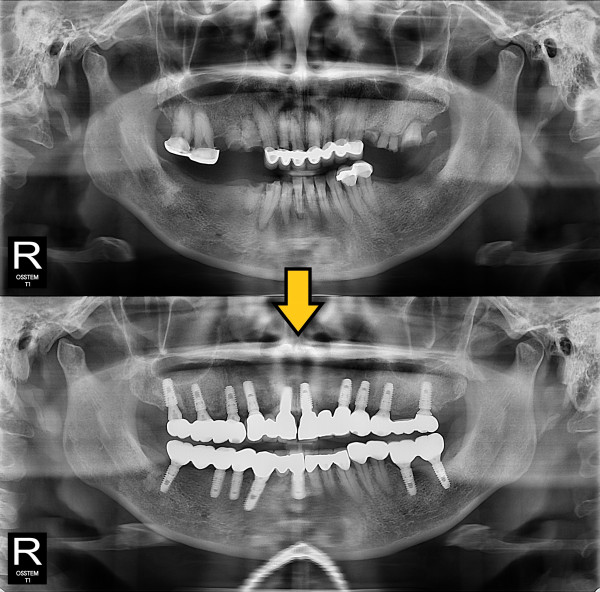

임플란트 전악 임플란트